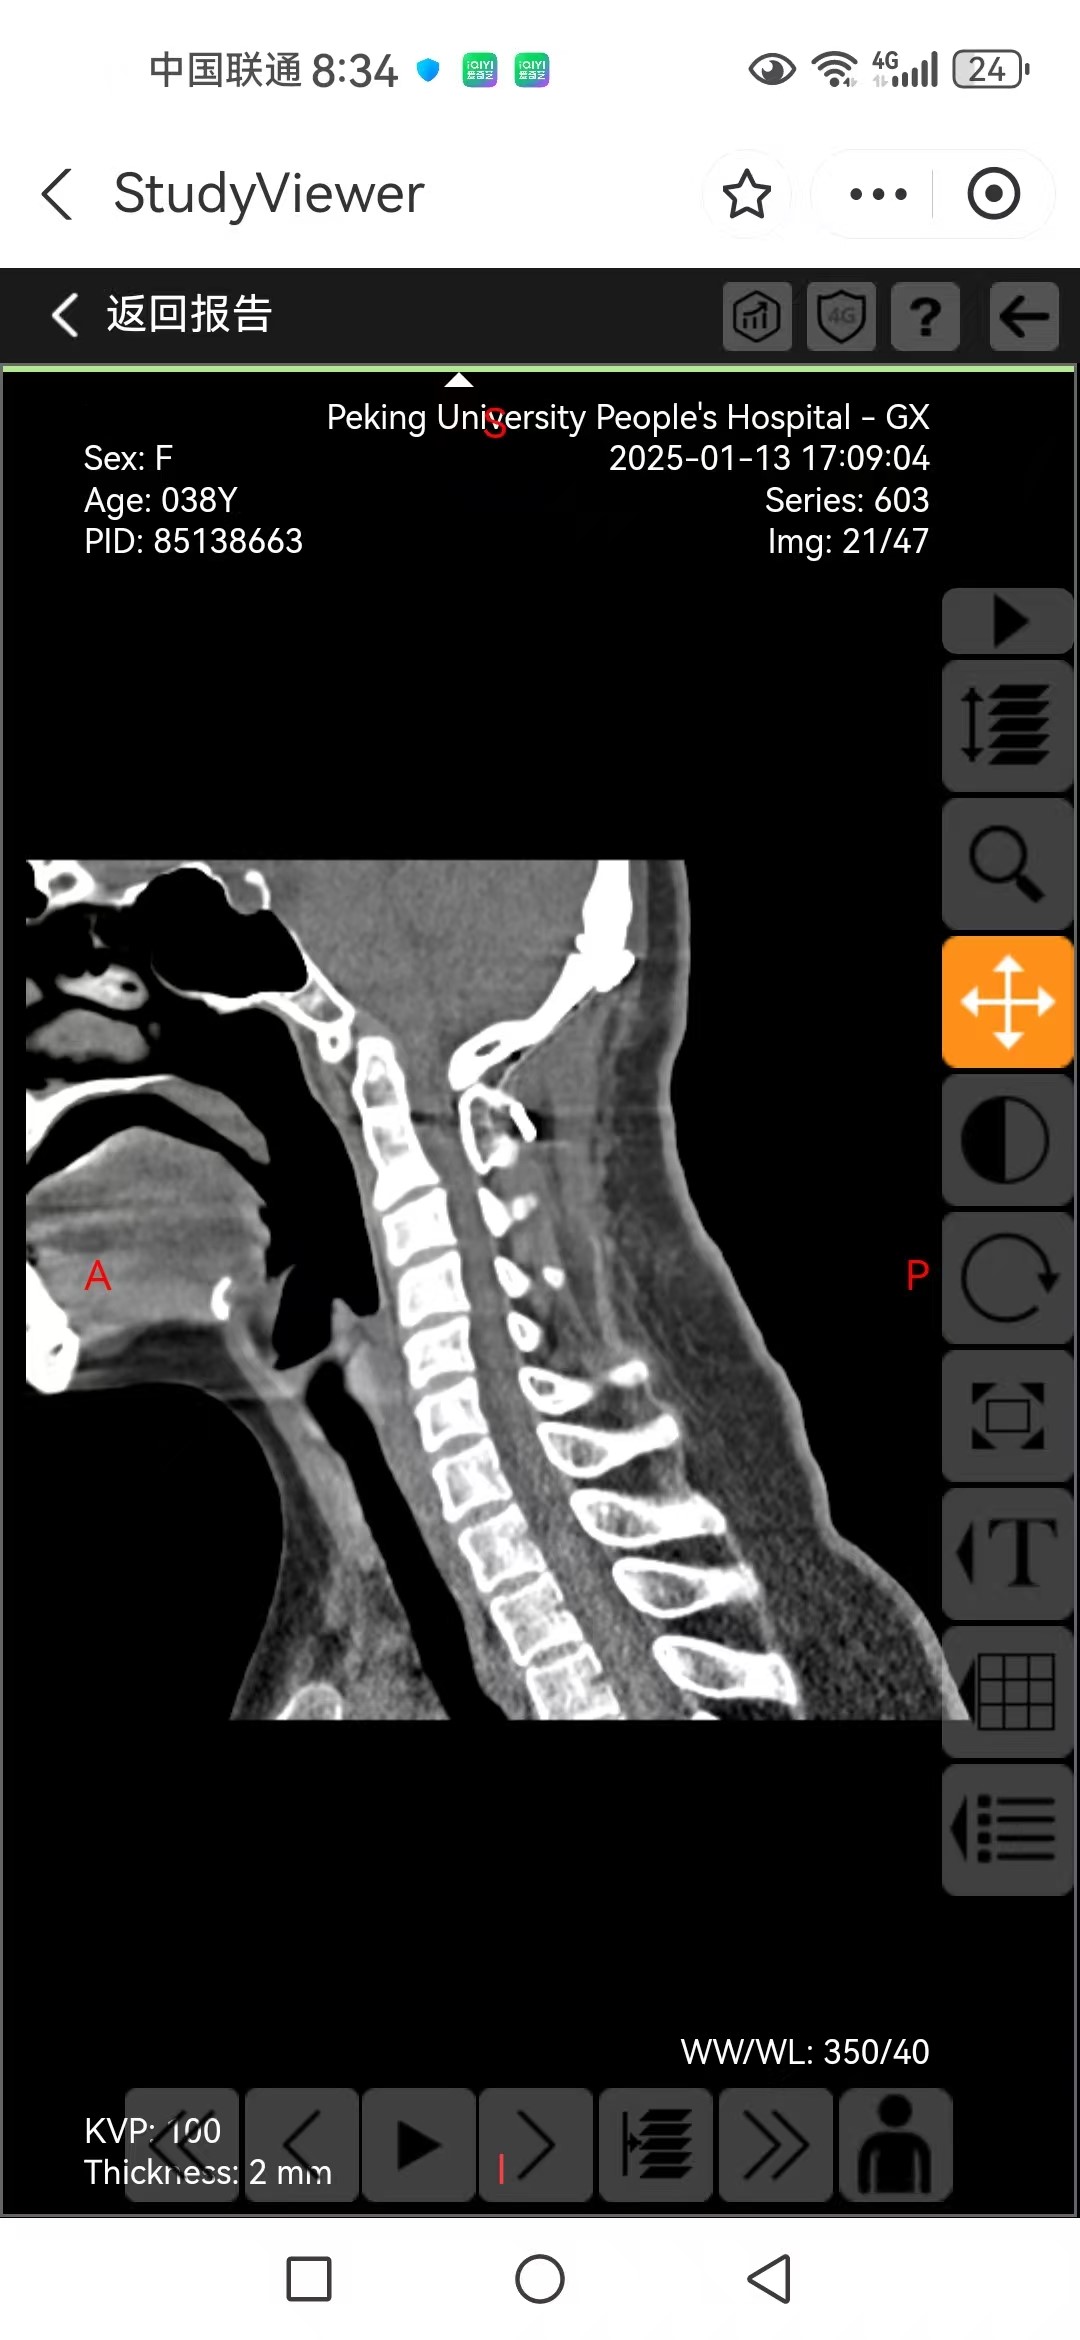

• 诊断:寰枢椎脱位,颅底凹陷

• 影像:

• 术后影像: